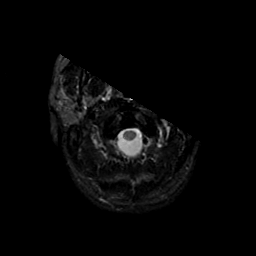

MR Study #9, April 14, 1991 -- Slice #0

[Home][Help][Clinical][Tour 1][Tour 2] Slice 0